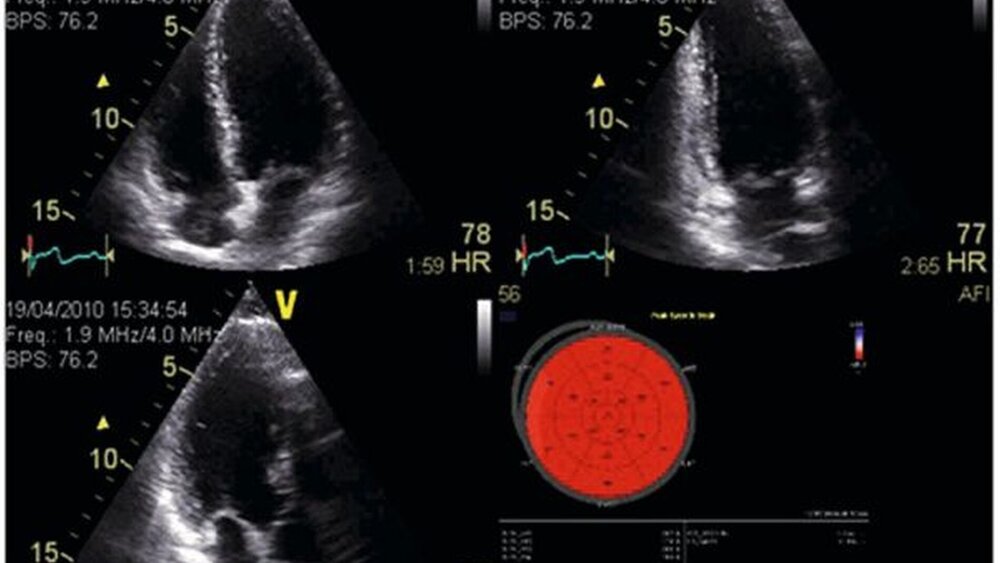

Alle sonstigen Daten wurden im Zuge des bereits bestehenden HIV-Herz-Protokolls [Neumann et al., 2007] erhoben. Der primäre kardiovaskuläre Endpunkt der hier vorgestellten Analyse war das Vorliegen einer kardiovaskulären Diagnose gemäß Patientenakte (Herzinsuffizienz, koronare Herzerkrankung, cerebrovaskuläre Erkrankung, periphere arterielle Verschlusskrankheit) und/oder eines abnormalen echokardiografischen Befunds (linksventrikuläre Auswurffraktion 50 Prozent, enddiastolischer linksventrikulärer Durchmesser 55 mm, regionale Wandbewegungsstörungen). Die Auswahl der echokardiografischen Kriterien orientierte sich an publizierten Empfehlungen [Jacobs und Crow, 2007].

Von den HIV-infizierten Patienten waren 100 (27 Prozent) kardiovaskulär auffällig im Sinne des primären Endpunkts. Die Häufigkeit nahm mit wachsender oraler Symptomlast stetig zu (Abbildung 3). Klammert man die 44 Patienten mit einer klinischen kardiovaskulären Diagnose aus, so hatten 56 (17 Prozent) der verbleibenden 328 Patienten eine echokardiografische Abnormalität. Die Häufigkeit eines solchen Befunds war wiederum signifikant mit der oralen Symptom last assoziiert (Abbildung 3). Dieses Ergebnis ist besonders bemerkenswert aufgrund der wechselseitig verblindeten Erhebung: Weder kannten die Patienten bei der Beantwortung des Fragebogens ihren echokardiografischen Befund, noch wusste der sonografische Untersucher um die Antworten der Patienten auf dem Mundgesundheitsfragebogen.